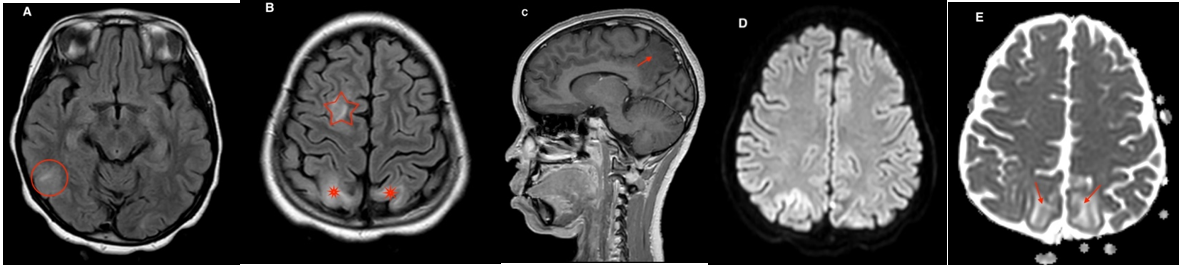

At J5 back from resuscitation, she showed a decrease in visual acuity, eye exam was normal. A magnetic resonance cerebral angiography was performed showing right lateral and temporo-frontal parieto-occipital lesions consistent with reversible posterior leukoencephalopathy (Figure 2-1).

Figure 2 – 1: A brain MRI in axial FLAIR (A and B), in sagittal T1 FFE with gadolinium injection (C) and DWI with ADC (E and F) found right temporal, and bilateral parietal and occipital lesions in hyper intense FLAIR (red circle and stars), without restriction on ADC mapping (red arrows), and showing no enhancement in T1 after injection (red arrow).

Neuroimaging has been considered to be central to the diagnosis of PRES [13].

In our case, at J5 back from resuscitation, she showed a decrease in visual acuity, eye exam was normal. A magnetic resonance cerebral angiography was performed showing right lateral and temporo-frontal parieto-occipital lesions consistent with reversible posterior leukoencephalopathy.

Various case series have described imaging abnormalities in the parieto-occipital region (in 65 to 99% of cases), frontal region (in 54 to 88%), temporal region (in 68%). [16,17]

MRI monitoring of brain injuries is crucial, not only to confirm the diagnosis of PRES, but also to assess the effectiveness of treatment.